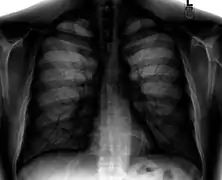

Chest radiograph

A normal posteroanterior (PA) chest radiograph of someone without any signs of injury. Dx and Sin stand for "right" and "left" respectively.

A chest radiograph, called a chest X-ray (CXR), or chest film, is a projection radiograph of the chest used to diagnose conditions affecting the chest, its contents, and nearby structures. Chest radiographs are the most common film taken in medicine.